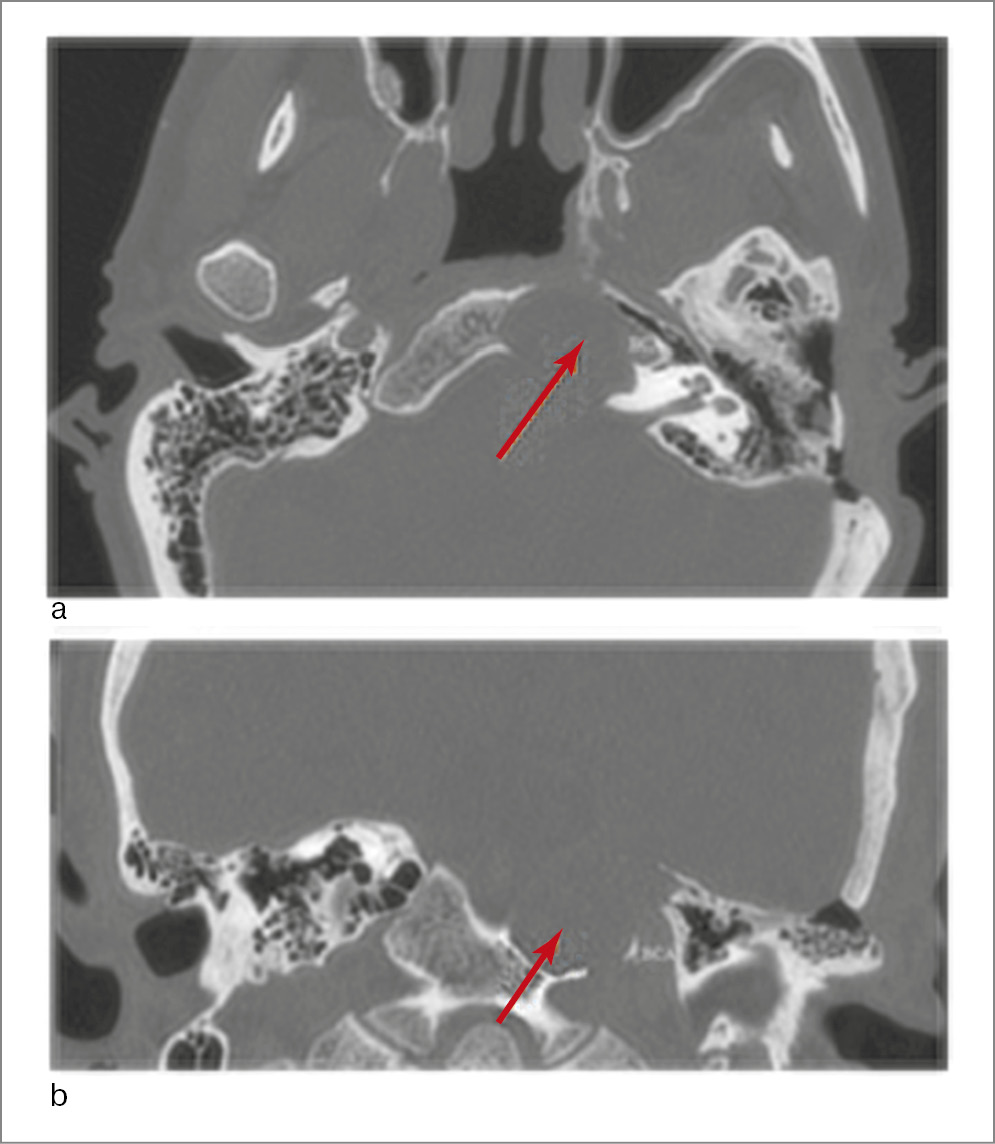

Пациент А., 64 года, поступил в январе 2021 г. в отделение патологии уха и основания черепа ФГБУ НМИЦО с жалобами на снижение слуха на левое ухо, двоение в глазах, шум в голове и левом ухе, головокружение, периодические эпизоды потери сознания. Со слов пациента, в 2016 г. отметил впервые диплопию. С 2017 г. появились приступы периодического системного головокружения, двоение в глазах, эпизоды кратковременной потери сознания. С 2019 г. беспокоит снижение слуха на левое ухо. Из анамнеза хронические отиты пациент отрицает. Выполнены КТ височных костей, МРТ головного мозга, по данным которых выявлено новообразование пирамиды левой височной кости (рис. 7, 8). Отомикроскопия: AD – заушная область без особенностей; НСП узкий свободный, барабанная перепонка серая, дефектов нет; AS – заушная область без особенностей; НСП узкий свободный, барабанная перепонка серая, дефектов нет. Спонтанного и прессорного нистагма нет. Функция мимической мускулатуры лица сохранена. Тональная пороговая аудиометрия при поступлении: двусторонняя сенсоневральная тугоухость 1-й степени (рис. 9).

Рис. 7. КТ височных костей: определяется объемное образование петрокливальной области с разрушением костного канала горизонтального отдела левой сонной артерии, левого ската: а – аксиальная проекция; b – коронарная проекция.